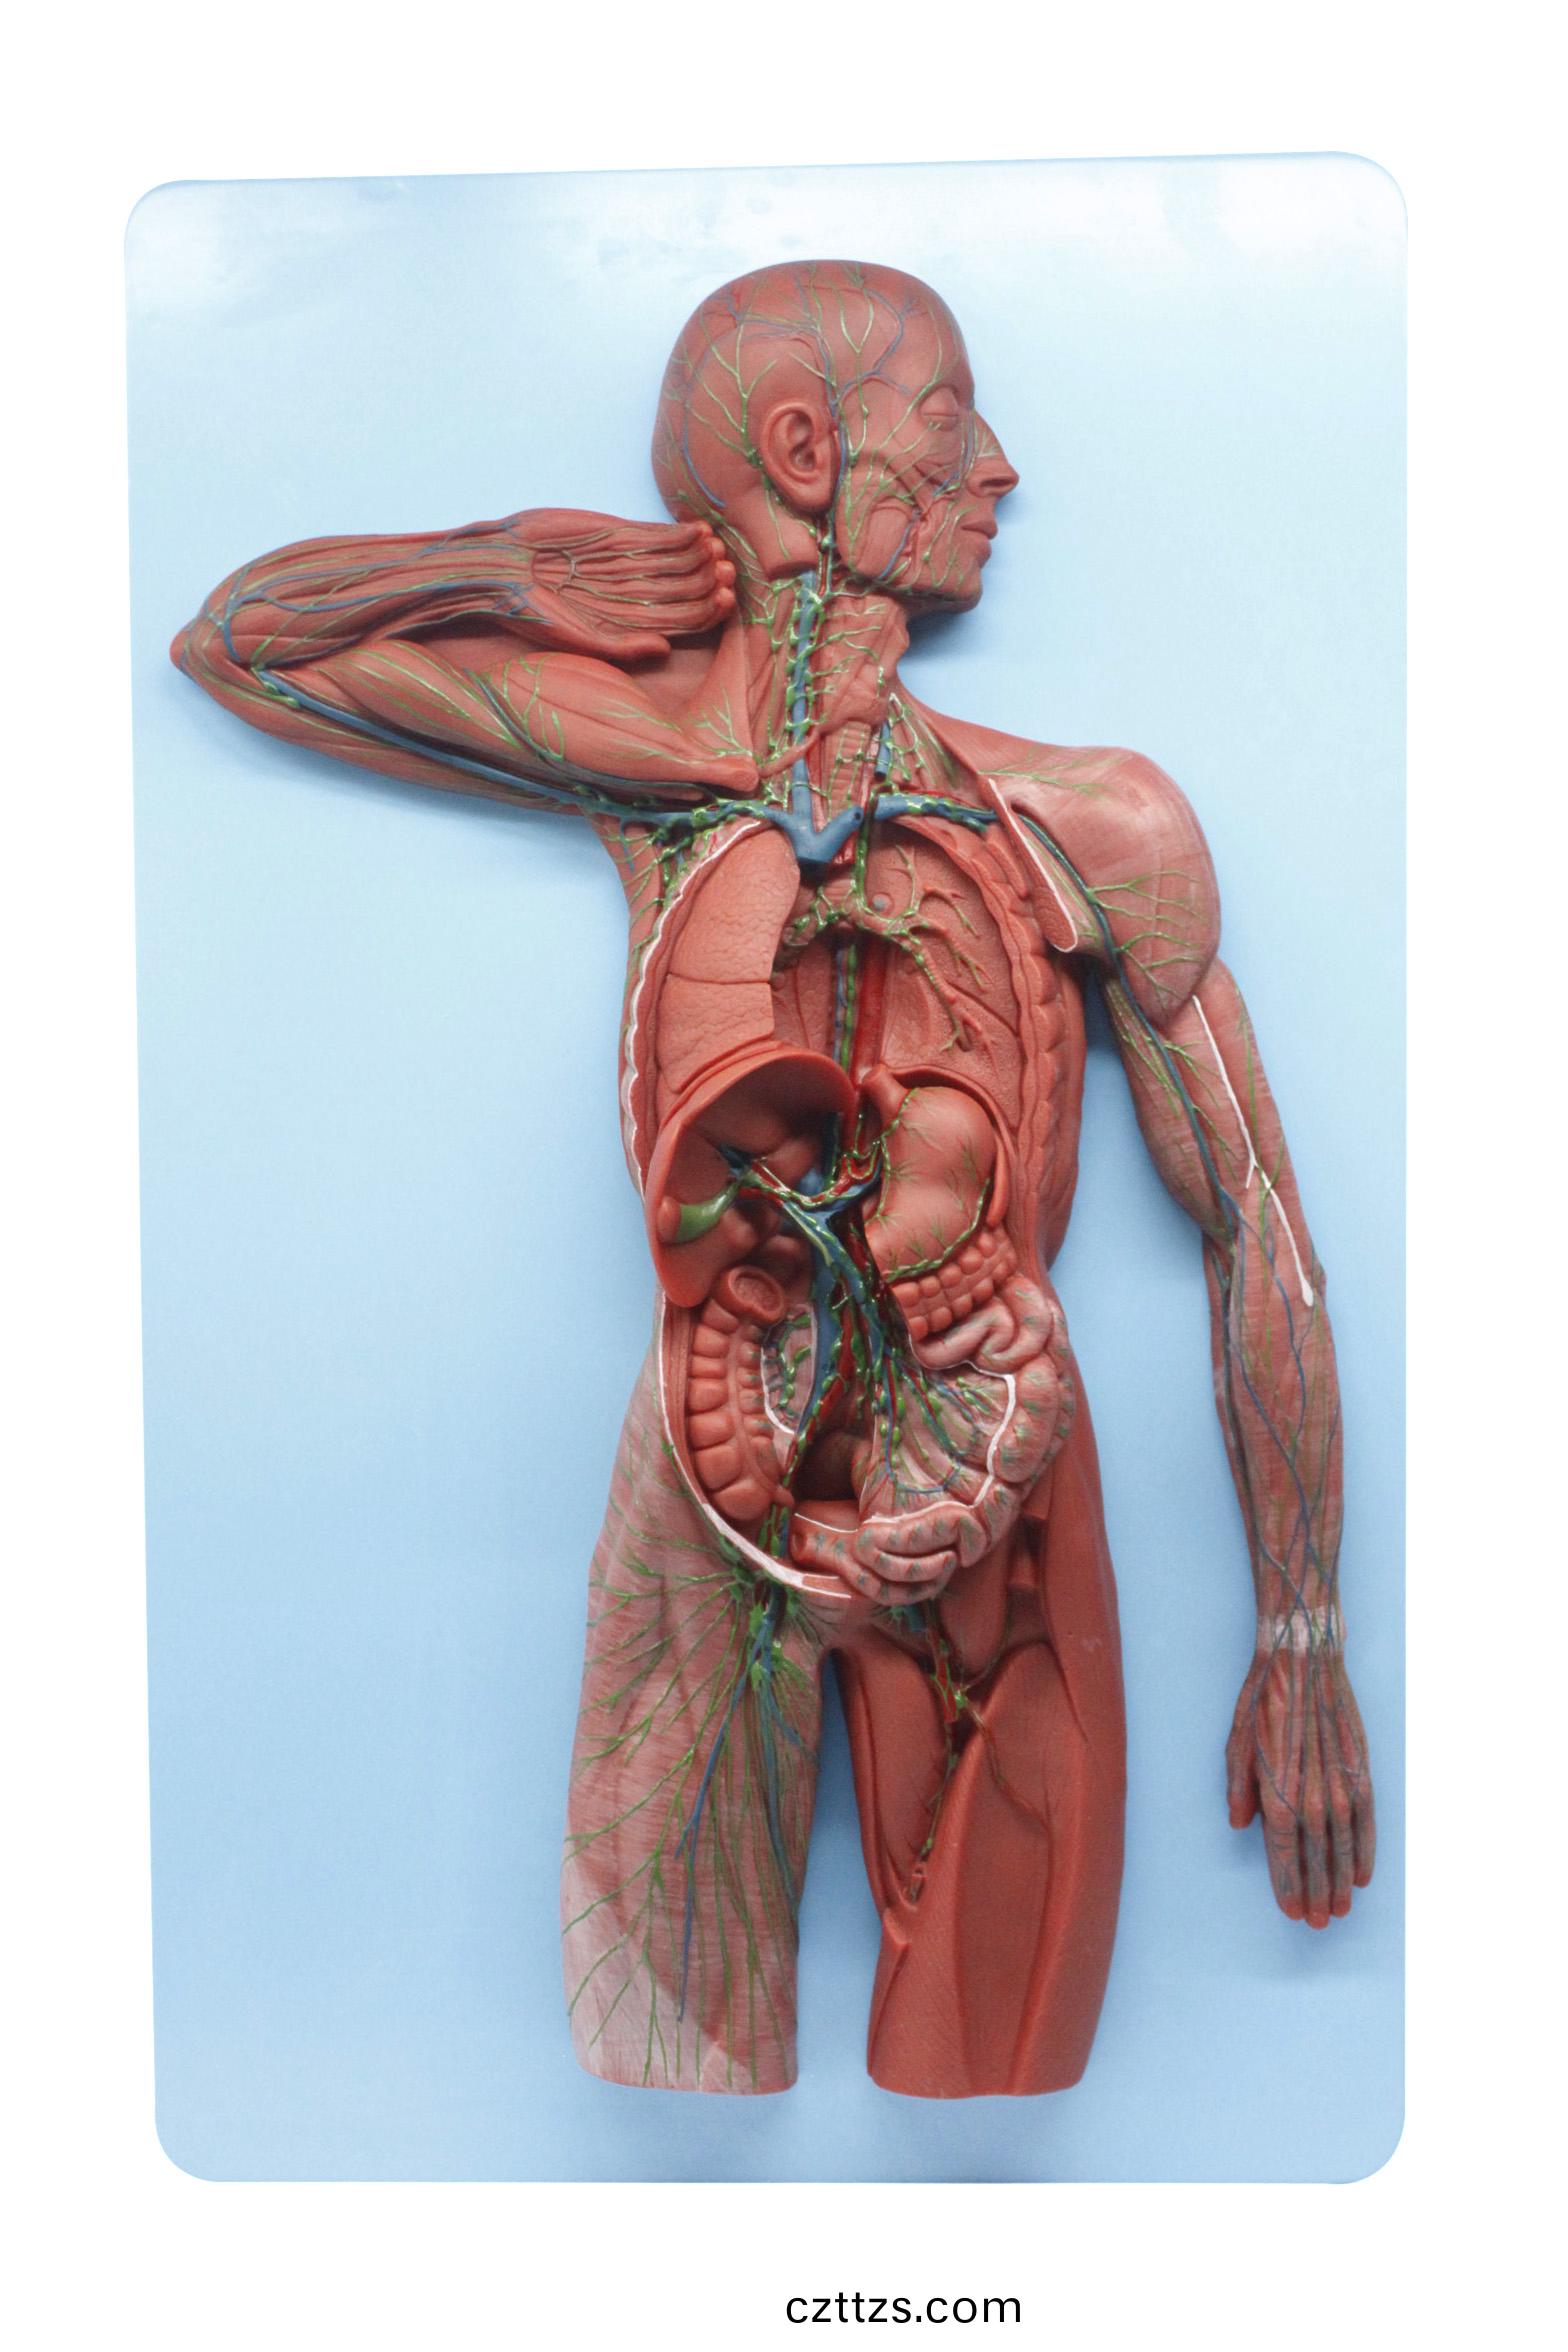

痳巴係統糢型

産品編號:HAM0176

功能特點:●顯示動靜衇及痳巴循環●尺寸:高76 5CM 寬......